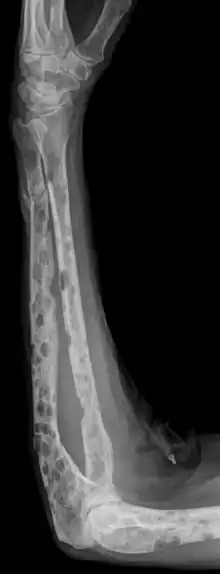

La radiographie du squelette montre très fréquemment des lésions osseuses de type ostéolyse.

La tomodensitométrie à faible dose de tous le corps est plus sensible que la radiographie conventionnelle pour décrire les aspects ostéolytiques ; elle est recommandée depuis 2015 en Europe comme nouvelle norme pour détecter les lésions lytiques du grade 1A du myélome[38].